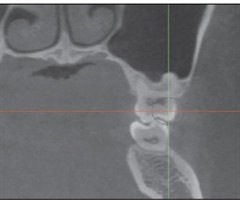

无托槽隐形矫治上颌扩弓效率的影响因素

[摘要]目的探究无托槽隐形矫治(CAT)过程中上颌扩弓效率的影响因素。方法筛选54名上颌扩弓矫治的非拔牙CAT患者,收集其基线数据,通过锥形束计算机断层扫描(CBCT)测量其牙冠和牙根长度,模型重叠测量其上颌扩弓效率和转矩变化,通过线性分析...